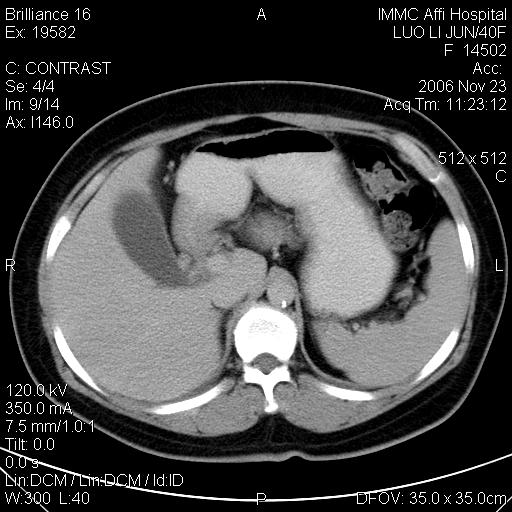

标题: CT5664:我也发一个肝脏的片子大家看看

很典型的肝癌。

速升速降,典型肝癌.

是啊,典型的早出早归!

快进快出典型肝癌.

快进快出,肝癌

很好的片子,可惜增强做的比较失败,a期时间没有把我好,实际到了静脉早期了,否则会更典型。